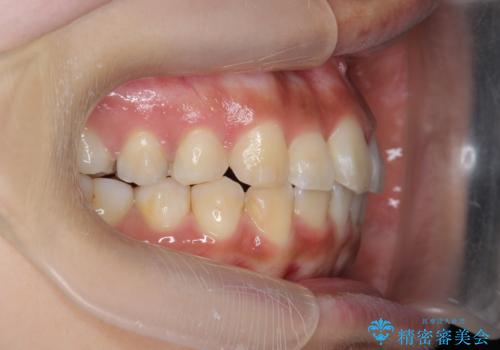

- 前歯の目立つねじれを矯正治療で治したい、と来院されました。

マウスピース矯正を始める前に、ねじれを取るのが短期間で済む部分ワイヤー小矯正を行うことで、全体的な治療期間を短くする治療計画を実行していきます。

前歯のねじれはマウスピース矯正の苦手な動きになり、治療期間が長くなる原因になりやすいです。